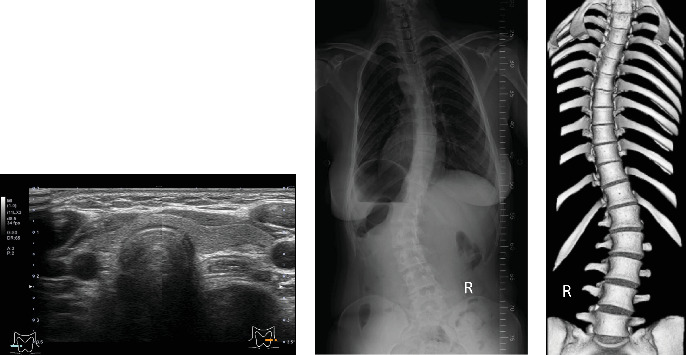

背景:家族性低钙性高钙血症3型(FHH3)是一种罕见的遗传性疾病,由AP2S1基因杂合突变引起,以钙(Ca)敏感受体(CaSRs)细胞内信号转导受损导致低钙尿和高钙血症为特征。所有受影响的患者在编码AP2σ1的Arg15残基上都存在杂合错义突变。病例介绍:一名21岁女性在脊柱侧凸手术术前检查中发现高钙血症和骨密度降低。她有发育障碍,尿液分析显示低钙尿。基因检测显示AP2S1基因杂合突变(p.a g15leu),诊断为FHH3。在本病例中,我们研究了新批准的CaSR激动剂evocalcet的作用。evocalcet治疗可使血清钙水平逐渐降低并恢复正常,促进骨代谢改善,无严重不良事件发生。结论:Evocalcet可能是治疗症状性FHH3的有希望的候选药物。

Background: Familial hypocalciuric hypercalcemia type 3 (FHH3) is a rare hereditary disorder caused by a heterozygous AP2S1 gene mutation, characterized by hypocalciuria and hypercalcemia due to impaired intracellular signal transduction of calcium (Ca)-sensing receptors (CaSRs). All affected patients harbored a heterozygous missense mutation at the Arg15 residue of the encoded AP2σ1. Case Presentation: A 21-year-old female was referred to our hospital with hypercalcemia and reduced bone mineral density (BMD) detected during a preoperative examination for scoliosis surgery. She had a developmental disorder and exhibited hypocalciuria on urinalysis. Genetic testing revealed a heterozygous AP2S1 gene mutation (p.Arg15Leu), and the patient was diagnosed with FHH3. In the present case, we investigated the effects of evocalcet, a newly approved CaSR agonist. Treatment with evocalcet gradually decreased and normalized the serum Ca level, and promoted improvements in bone metabolism, without serious adverse events. Conclusion: Evocalcet may be a promising therapeutic candidate for symptomatic FHH3.